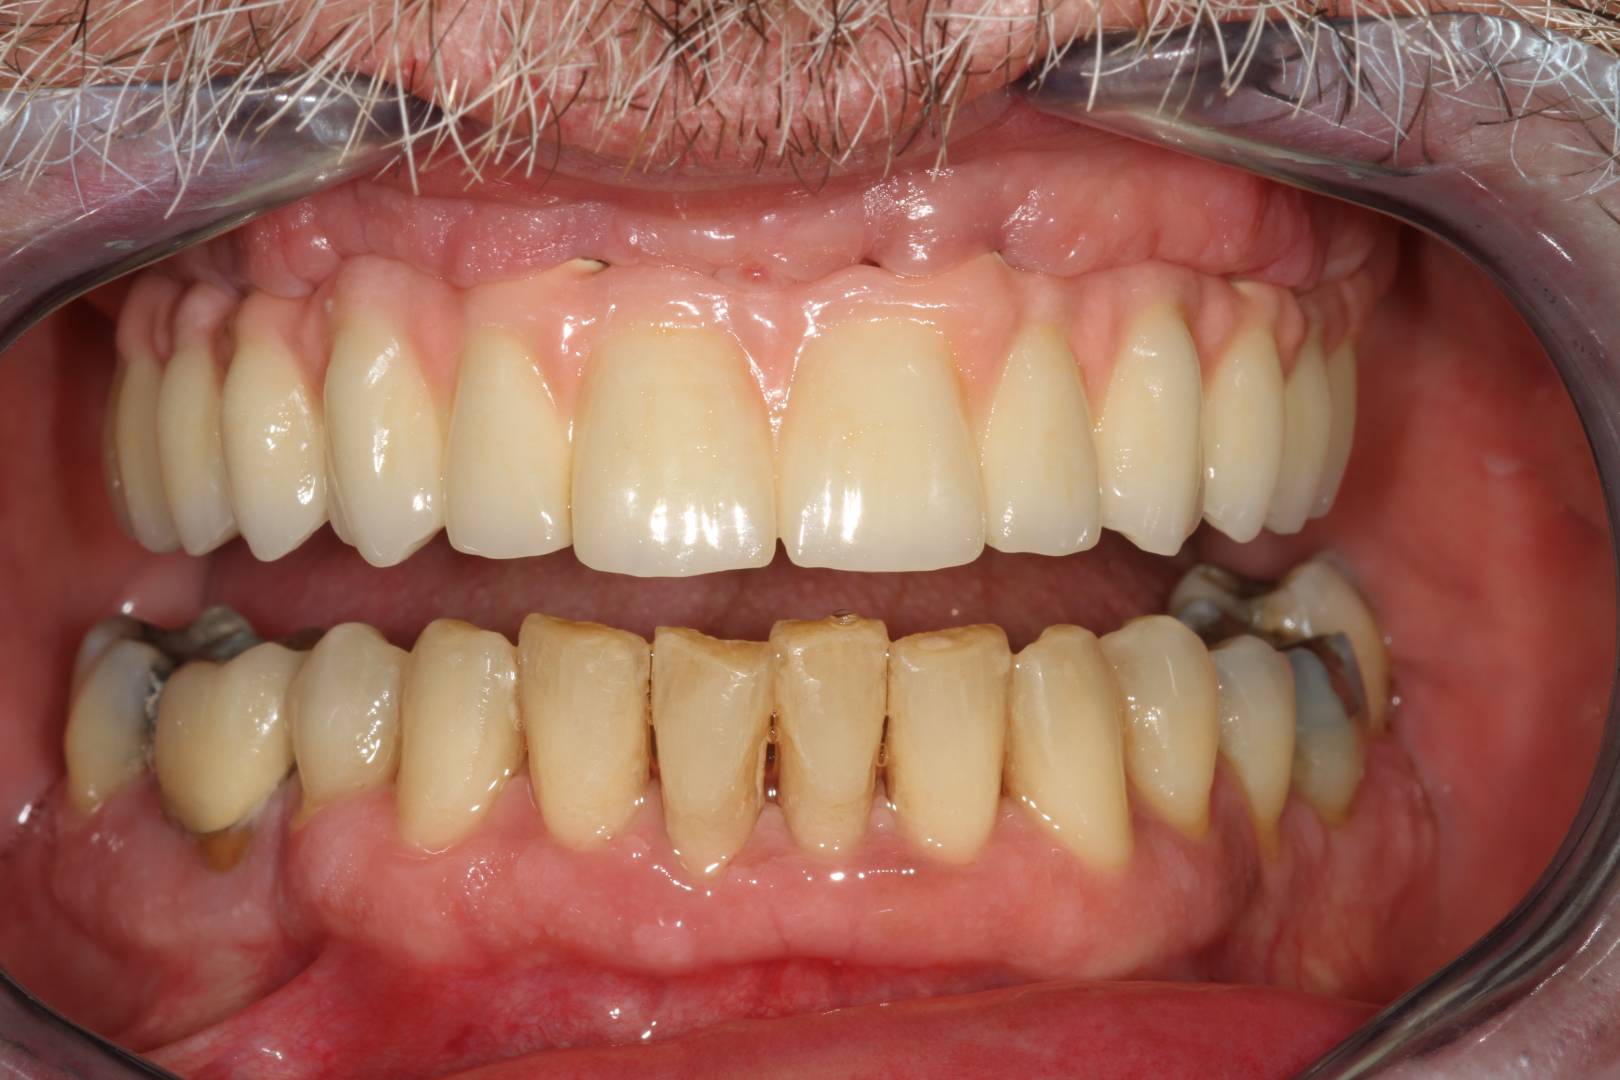

All-on-4 előtte-utána

Először helyi érzéstelenítést adunk, majd 4 titánium implantátumot helyezünk be. Kettőt egyenesen az állcsont elülső és kettőt ferdén a hátsó területére. Ezek fogják támasztani az állkapocsba rögzített teljes hidat. Az így behelyezett híd természetesnek hat, hosszú ideig jól illeszkedik, nem mozog, ezáltal garantálja a természetes fogak funkcionalitását és harapási minőségét.

Az első kezelést követően már egy fixen rögzített hídpótlás készül, amelyet használni tud addig, amíg az implantátumok megfelelően be nem ágyazódnak az állcsontba. Az ideiglenes híd már ebben az átmeneti, gyógyulási periódusban is jelentősen javítja az életminőségét. Ezalatt az időszak alatt is már fog tudni nyugodtan enni, beszélni és mosolyogni is.